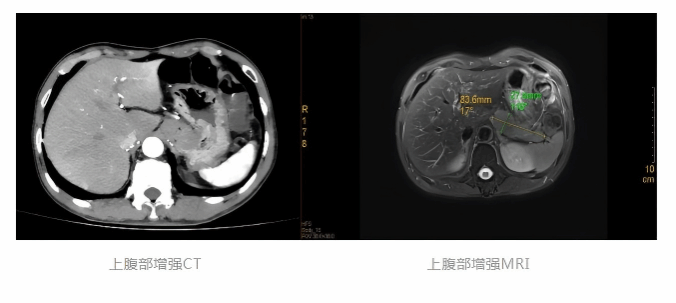

入院后,医疗团队迅速为徐先生完善相关检查,先后完成腹部增强CT、腹部增强MRI及超声胃镜等精准评估项目。影像检查结果清晰提示:患者胃底贲门部存在一巨大外生型肿块,考虑平滑肌瘤或胃间质瘤可能性大。